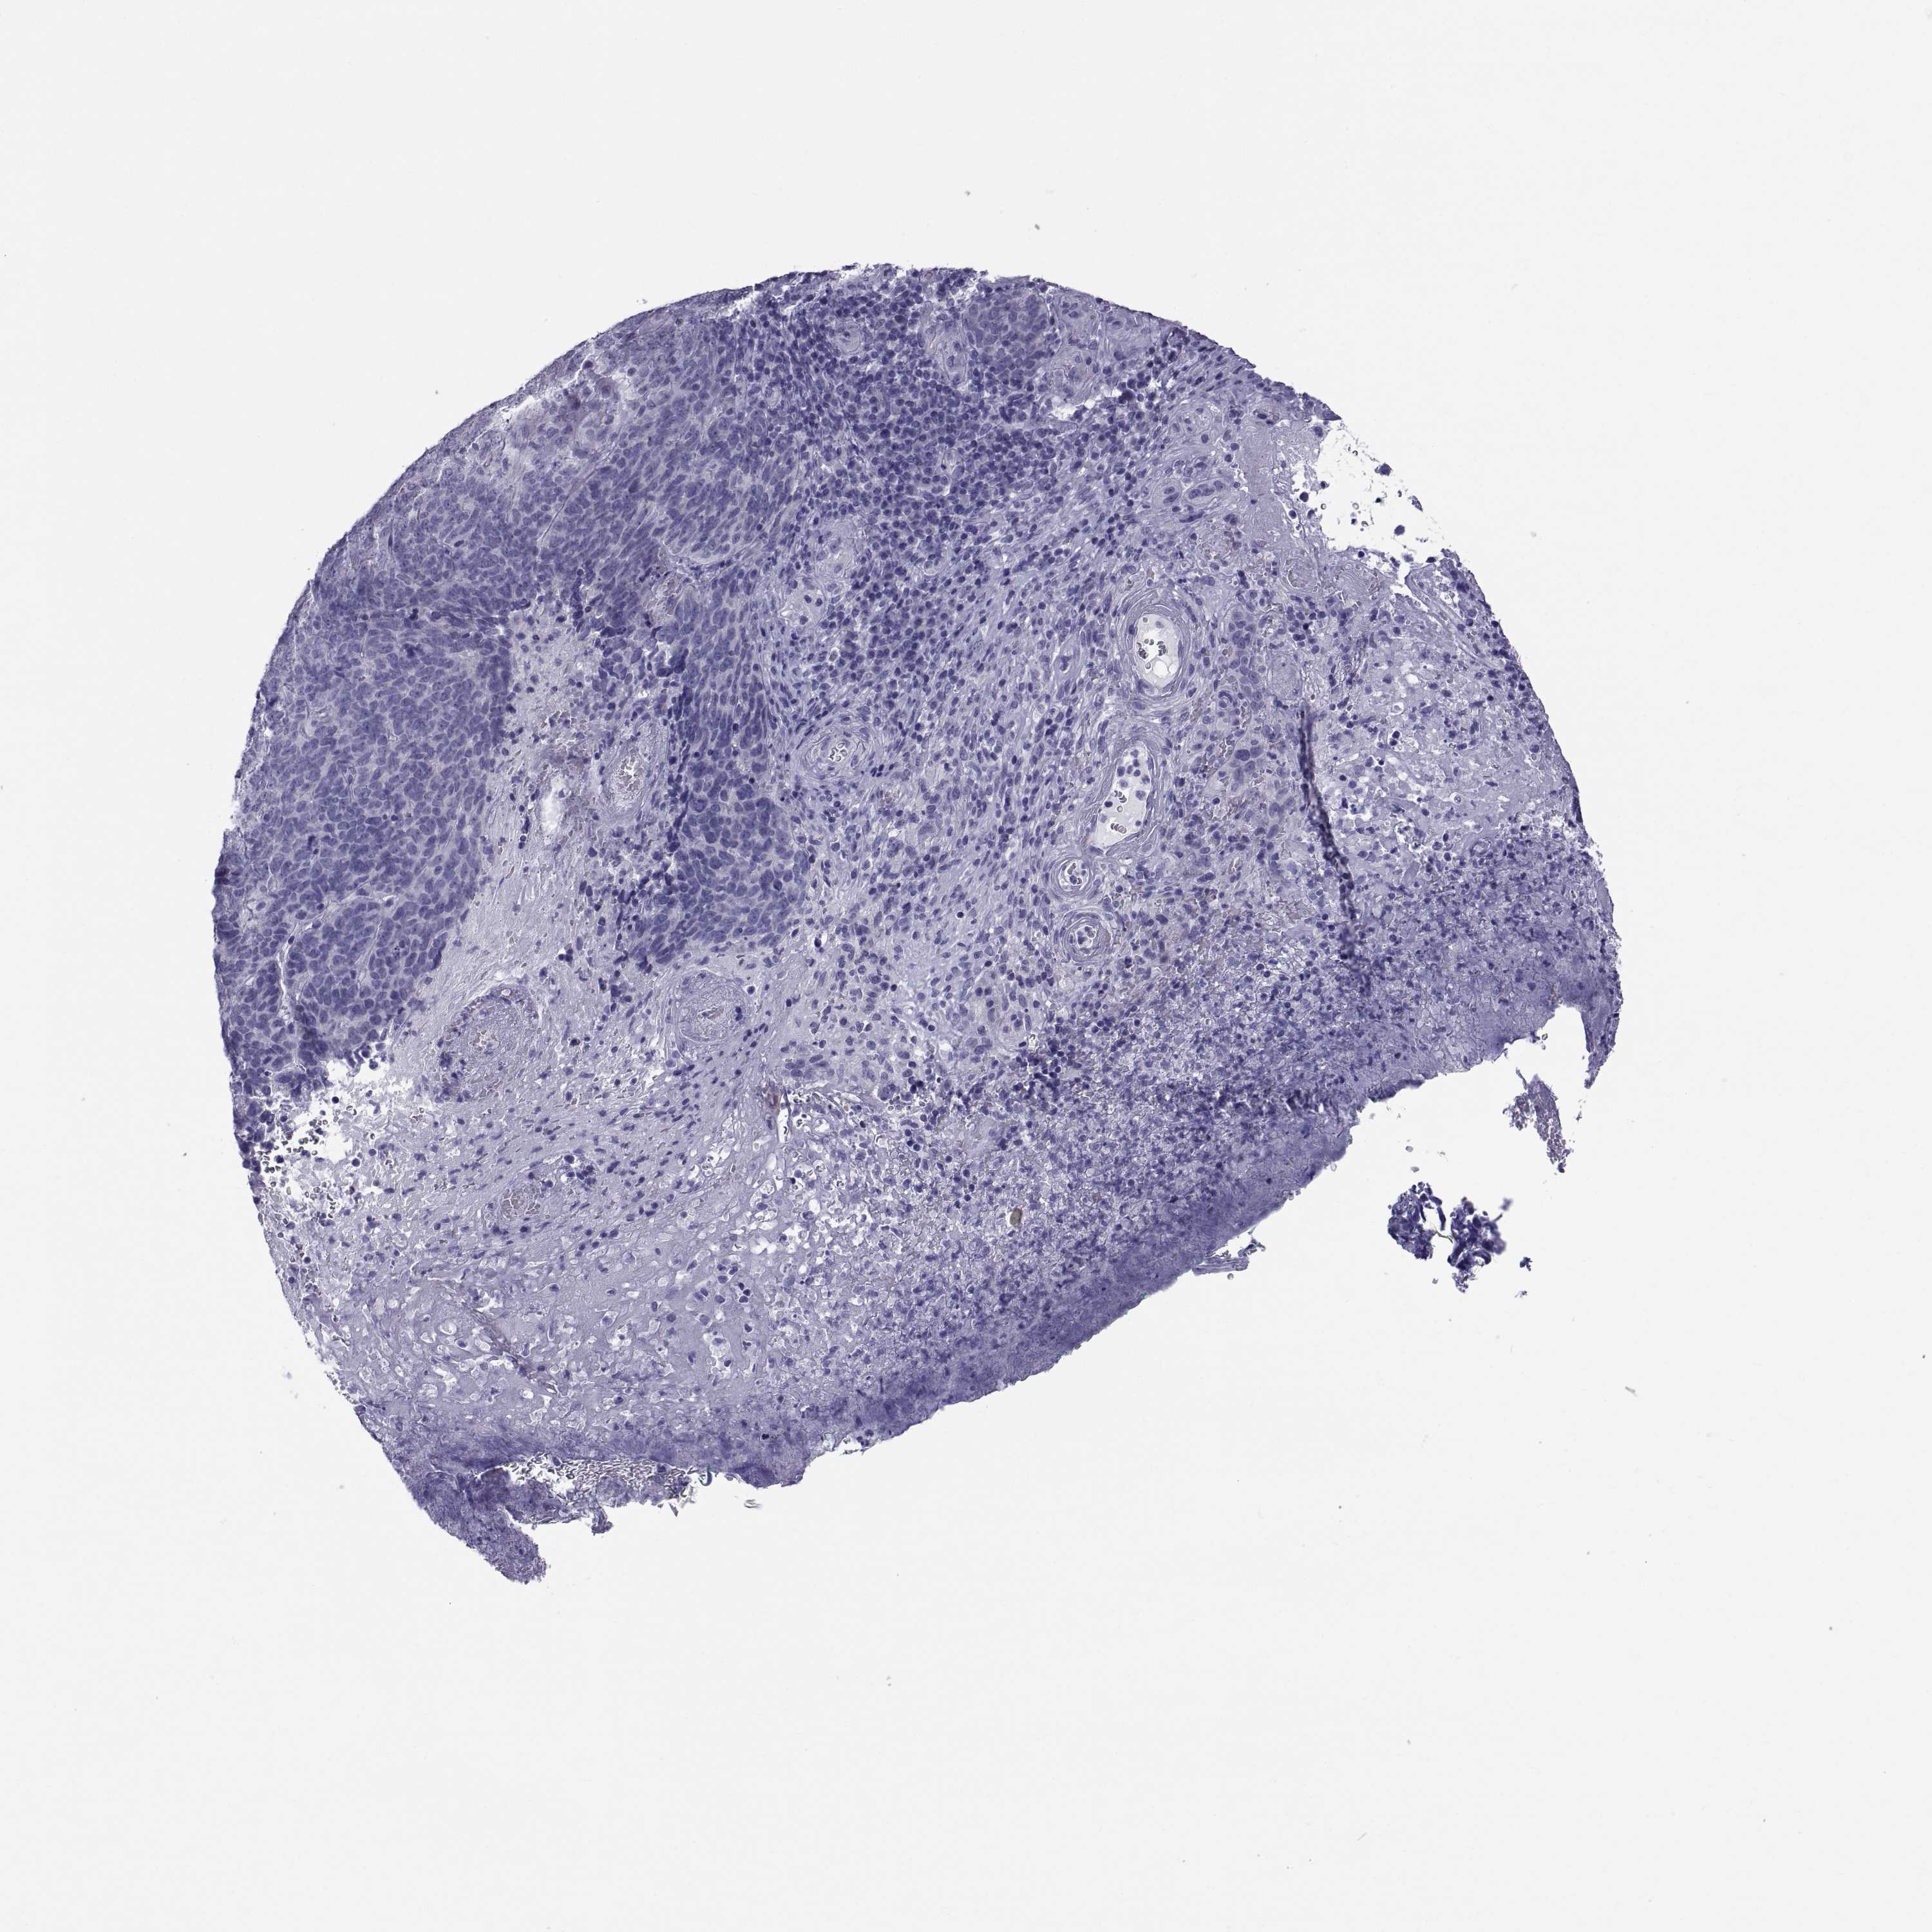

CANCER SKIN CANCER Show tissue menu

Basal cell and squamous cell cancer

SKIN CANCER - Protein expressioni

A mouse-over function shows sample information and annotation data. Click on an image to view it in a full screen mode. Samples can be filtered based on level of antibody staining by selecting one or several of the following categories: high, medium, low and not detected. The assay and annotation is described here.

Each image is clickable and will lead to virtual microscopy that enables deeper exploration of all samples and also displays staining intensity scores, fraction scores and subcellular localization as well as patient and tissue information for each sample.

Antibody HPA044175

Antibody HPA059465

Basal cell carcinoma

Squamous cell carcinoma, NOS